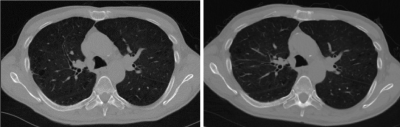

A 65-year- old male with chronic obstructive pulmonary disease presented to his primary care physician with symptoms of dysphagia and odynophagia. He was an active smoker with 96 pack-year smoking history. He was thought to have gastroesophageal reflux for which omeprazole was given with some clinical improvement but given his symptoms along with a heavy smoking history, a chest CT to screen for lung malignancy was ordered. The CT showed a distal tracheal abnormality on the right (Figure 1A). Secretions or a tracheal wall abnormality were thought to be possible causes of the abnormality. A repeat CT scan was planned and performed 4 months later. During this interval, the patient complained of development of cough with yellowish phlegm production. A repeat CT showed a persistent presence of a distal right tracheal wall lesion (Figure 1B).

Figure 1. A. CT chest showing a right distal trachea lesion. B. A repeat CT chest showing a persistent right distal trachea lesion.